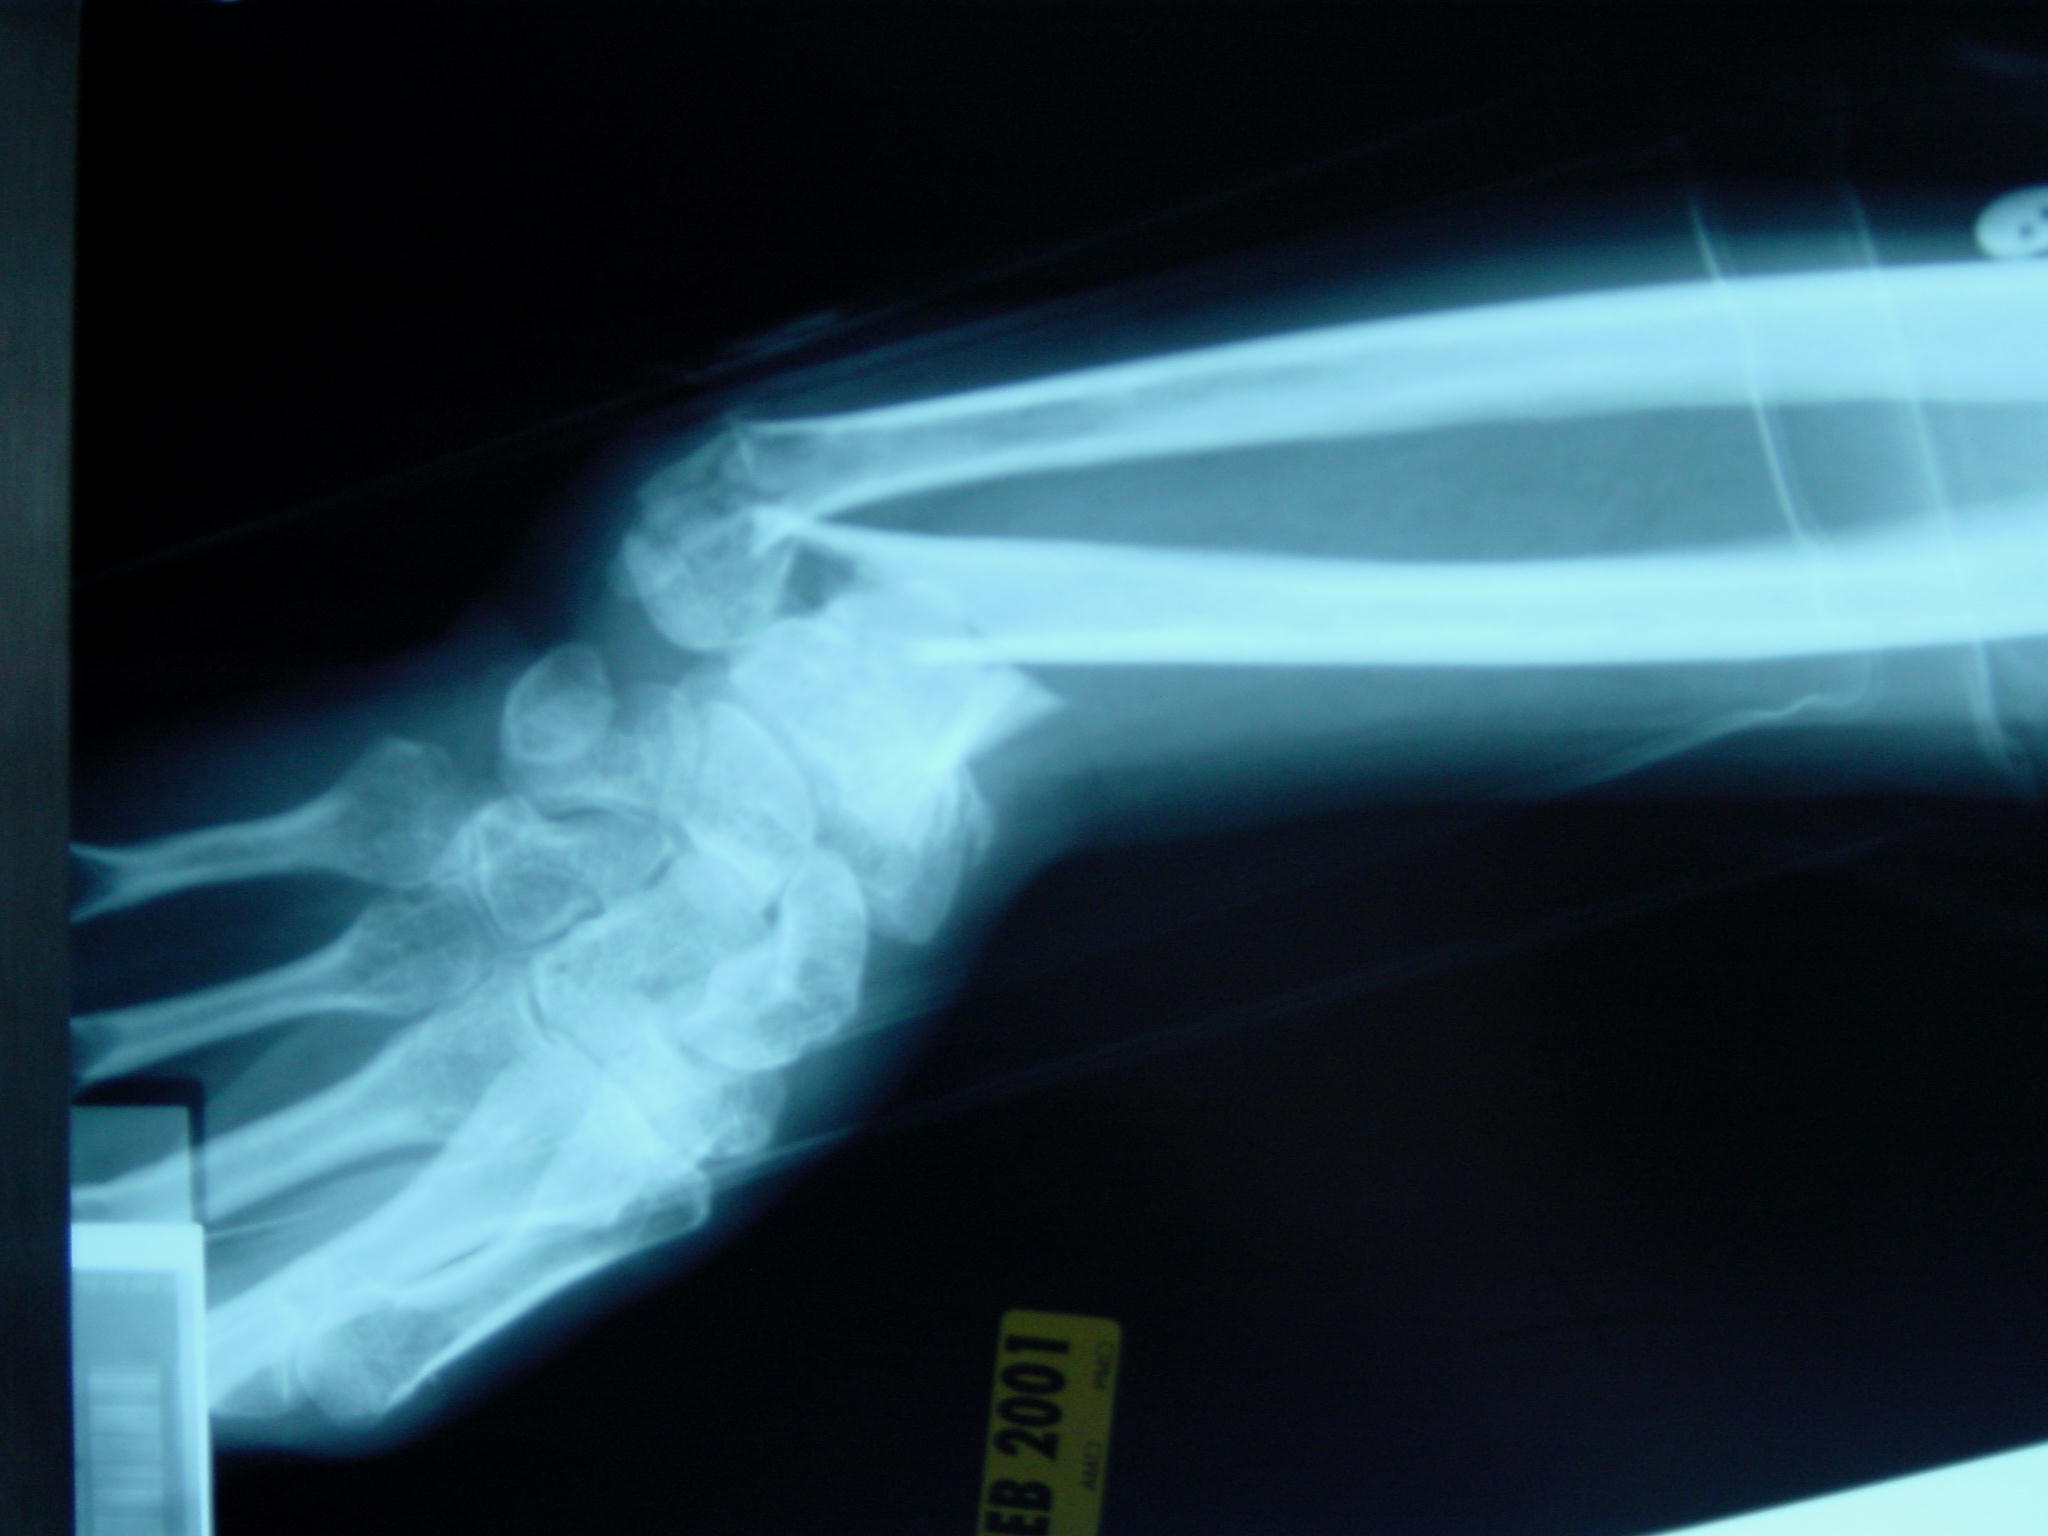

Uređaj se koristi dvadeset minuta dnevno kod kuće, a treba proći oko mjesec i pol da se rezultati vide na rendgenskoj snimci. (MJ)